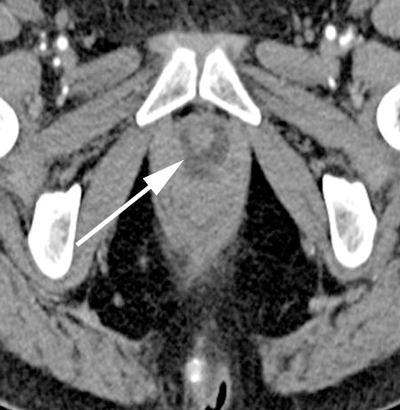

With CT imaging, diverticula appear as hypointense periurethral cystic lesions, with wall thickening and enhancement [2]. They are usually identified at the level of the pubic symphysis (Figure 2). Using voiding CT urethrography, the diverticula may opacify upon post voiding imaging [2]. To a limited extent CT can characterise urethral abnormalities [2]. It can also identify associated complicating urethral calculi and gas within the diverticula and allows for regional staging of any urethral neoplasms [2]. The disadvantage of CT is the use of ionising radiation and it is rather insensitive for small diverticula [4]. Figure 2 demonstrates a urethral diverticulum on CT imaging. Note the low attenuation, thick walled cystic density structure around the urethra measuring 2.7 x 2.0cm.

Figure 2a: Axial CT.